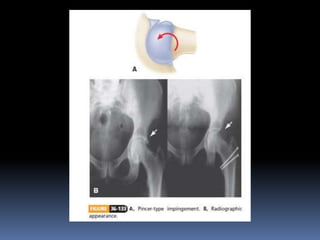

FEMOROACETABULAR IMPINGEMENT

 RADIOLOGICAL APPEARANCES-

 Plain x-rays are taken in AP & lateral view (frog leg)